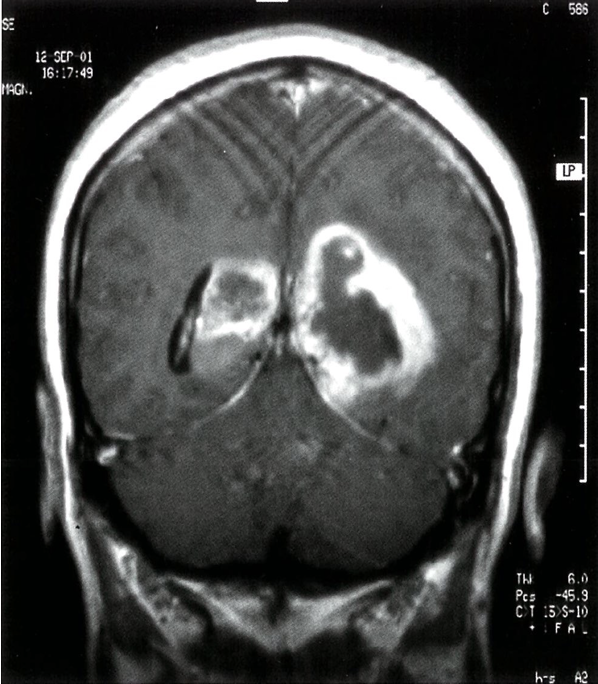

T1-weighted contrast-enhanced MRI: bihemisphere contrast enhancement lesion. There is peripheral contrast agent enhancement. The third ventricle is centrally located. The tumor is displacing the posterior horn of the lateral ventricle .